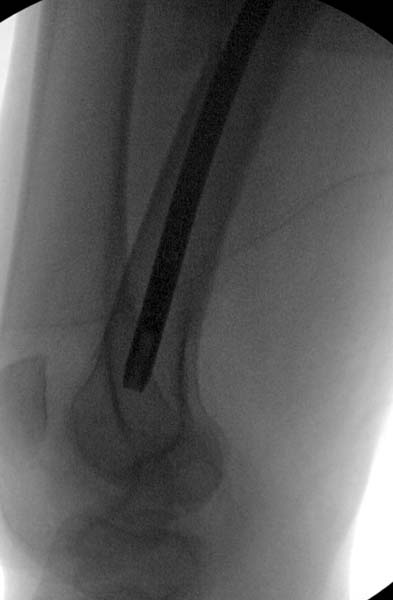

Больная стабильная после хирургических мероприятии и получив добро, приступили к закрытому вправлению таранной кости с укладкой наружного фиксатора. Затем укладка больную на бок и открытый остеосинтез перелома-вывиха головки бедра.

По характеру повреждения головка находится сзади и напрашивается задний Кохер-Лангенбек доступ, но в заднем доступе имеется риск повреждения магистрального кровоснабжения головки a. circumflexa. Более щадящая trochanteric flip (digastric osteotomy) сохранит кровоснабжение и дасть возможность работу при вывихнутом суставе.

Остеосинтез бедра не стали делать из-за множественных переломов ребер с ушибом грудной клетки и поэтом у закончили фиксацию бедра наружным фиксатором.